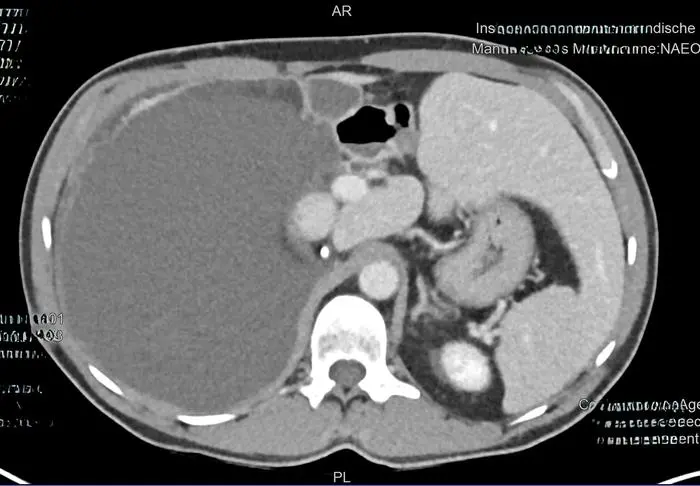

Anfang Dezember wurde einem Südburgenländer in der Klinik Oberwart ein seltener „Keimzellentumor“ entfernt. Dieser hatte Zähne und Haare. Herr M. berichtet wie aus einem „normalen Arztbesuch“ eine erstaunliche Diagnose wurde.

• Ein 50-jähriger Mann aus Südburgenland hatte einen seltenen 30 cm großen Keimzellentumor im Bauchraum, der Zähne und Haare enthielt.

• Der Tumor wurde entdeckt, nachdem der Mann wegen Atembeschwerden und Bauchschmerzen seinen Hausarzt aufsuchte und zum Ultraschall geschickt wurde.

• Der Tumor war gutartig, musste aber operativ entfernt werden, da er andere Organe verdrängte und die Gefahr bestand, dass er platzt.

• Die Operation war kompliziert, da der Tumor zwischen Leber, Niere, großer Körperarterie und Dickdarm lag.